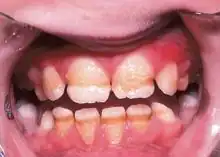

Enamel hypoplasia is a defect of the teeth in which the enamel is deficient in quantity,[1] caused by defective enamel matrix formation during enamel development, as a result of inherited and acquired systemic condition(s). It can be identified as missing tooth structure and may manifest as pits or grooves in the crown of the affected teeth, and in extreme cases, some portions of the crown of the tooth may have no enamel, exposing the dentin.[2] It may be generalized across the dentition or localized to a few teeth. Defects are categorized by shape or location. Common categories are pit-form, plane-form, linear-form, and localised enamel hypoplasia.[3][4][5] Hypoplastic lesions are found in areas of the teeth where the enamel was being actively formed during a systemic or local disturbance. Since the formation of enamel extends over a long period of time, defects may be confined to one well-defined area of the affected teeth. Knowledge of chronological development of deciduous and permanent teeth makes it possible to determine the approximate time at which the developmental disturbance occurred.[6] Enamel hypoplasia varies substantially among populations and can be used to infer health and behavioural impacts from the past. Defects have also been found in a variety of non-human animals.[7][8][9]

Irreversible enamel defects caused by an untreated celiac disease. They may be the only clue to its diagnosis, even in absence of gastrointestinal symptoms, but are often confused with fluorosis, tetracycline discoloration, or other causes.[10][11][12] The National Institutes of Health include a dental exam in the diagnostic protocol of celiac disease.[10]

Enamel hypoplasia is believed to result from the dysfunction of ameloblasts—enamel-producing cells—either for a short period of time or throughout their lifespan. Enamel hypoplasia has a wide variety of known causes. Some causes are hereditary and others are from environmental exposure. The severity and localization of disease presentation is dependent on the timing and stage of tooth development in which the defective enamel formation occurred.

Enamel hypoplasia is a risk factor for dental caries in children including early childhood caries (ECC), which continues to be a burden for many children. This association has been identified as significant and independent, and is believed that the formation of pits and missing enamel provides a suitable local environment for adhesion and colonization of cariogenic bacteria. Historically, enamel hypoplasia has been under-appreciated as a risk factor for ECC.

Developmental defects in enamel that affect tooth appearance in the esthetic zone (i.e. upper front teeth) may cause individuals to experience social embarrassment or anxiety regarding the appearance of their teeth.